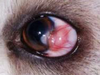

Mdx? Sequela?

Ciliary (Iridociliary) adenoma/carcinoma

Sequela = Glaucoma, hyphema, retinal detachment

DOGS >>>>>> cats

Most benign